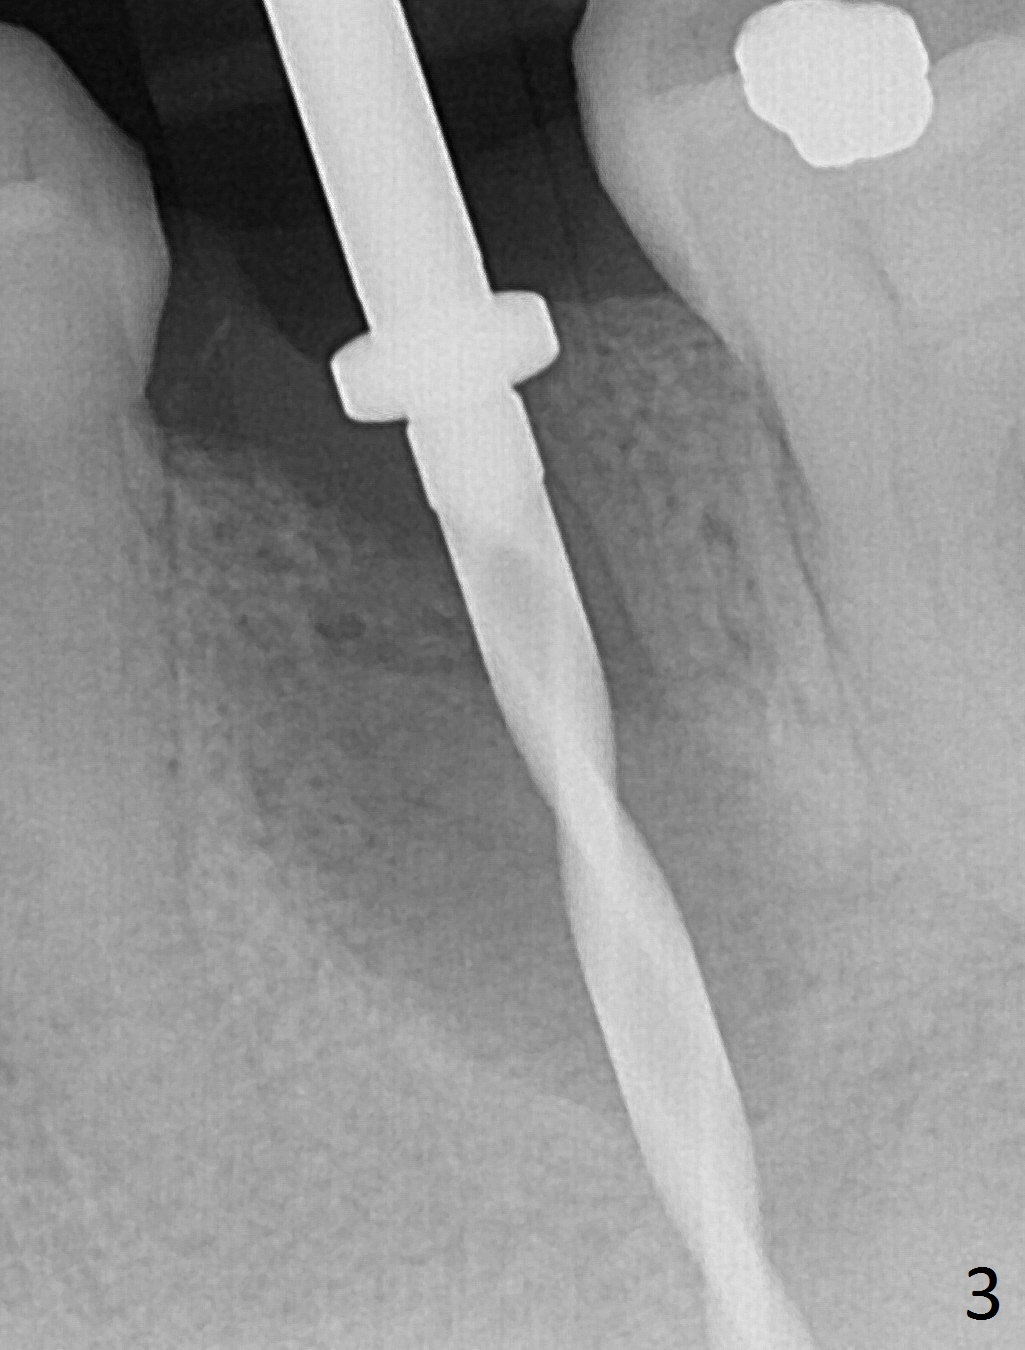

Extraction of the lower left 2nd premolar with vertical fracture (Fig.1,2 >) is easy because of peri-radicular radiolucency.  The apical end of the osteotomy is not shown with a 2 mm pilot drill (Fig.3) or a 3.8x18 mm implant (Fig.4) in place.  It appears that the implant is not placed deep enough.  Following 3-4 more turns of the implant and placement of a 5.5x4(3) mm abutment (Fig.5 A), allograft is placed (*).  A postop panoramic X-ray is taken (Fig.6); the osteotomy could have been deepened to reduce the possibility of periimplantitis.  Retrospectively, the panoramic X-ray should be taken after use of the pilot drill. The bone around the implant appears to have regenerated 4 months postop (Fig.7,8).  Bone density appears to continue increasing 9 months postop (i.e., 4.5 months post cementation, Fig.9).  Bone loss is minimal 2 years post cementation (Fig.10).